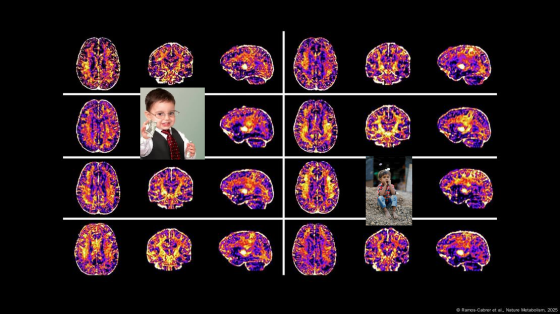

LA MERITOCRACIA QUE NUNCA FUE: Estudio científico revela que la desigualdad social altera el cerebro infantil y deteriora la salud mental

La ciencia pone en claro la desigualdad de la carrera del mérito. Por Tomás Palazzo para Noticias La Insuperable Un … Más